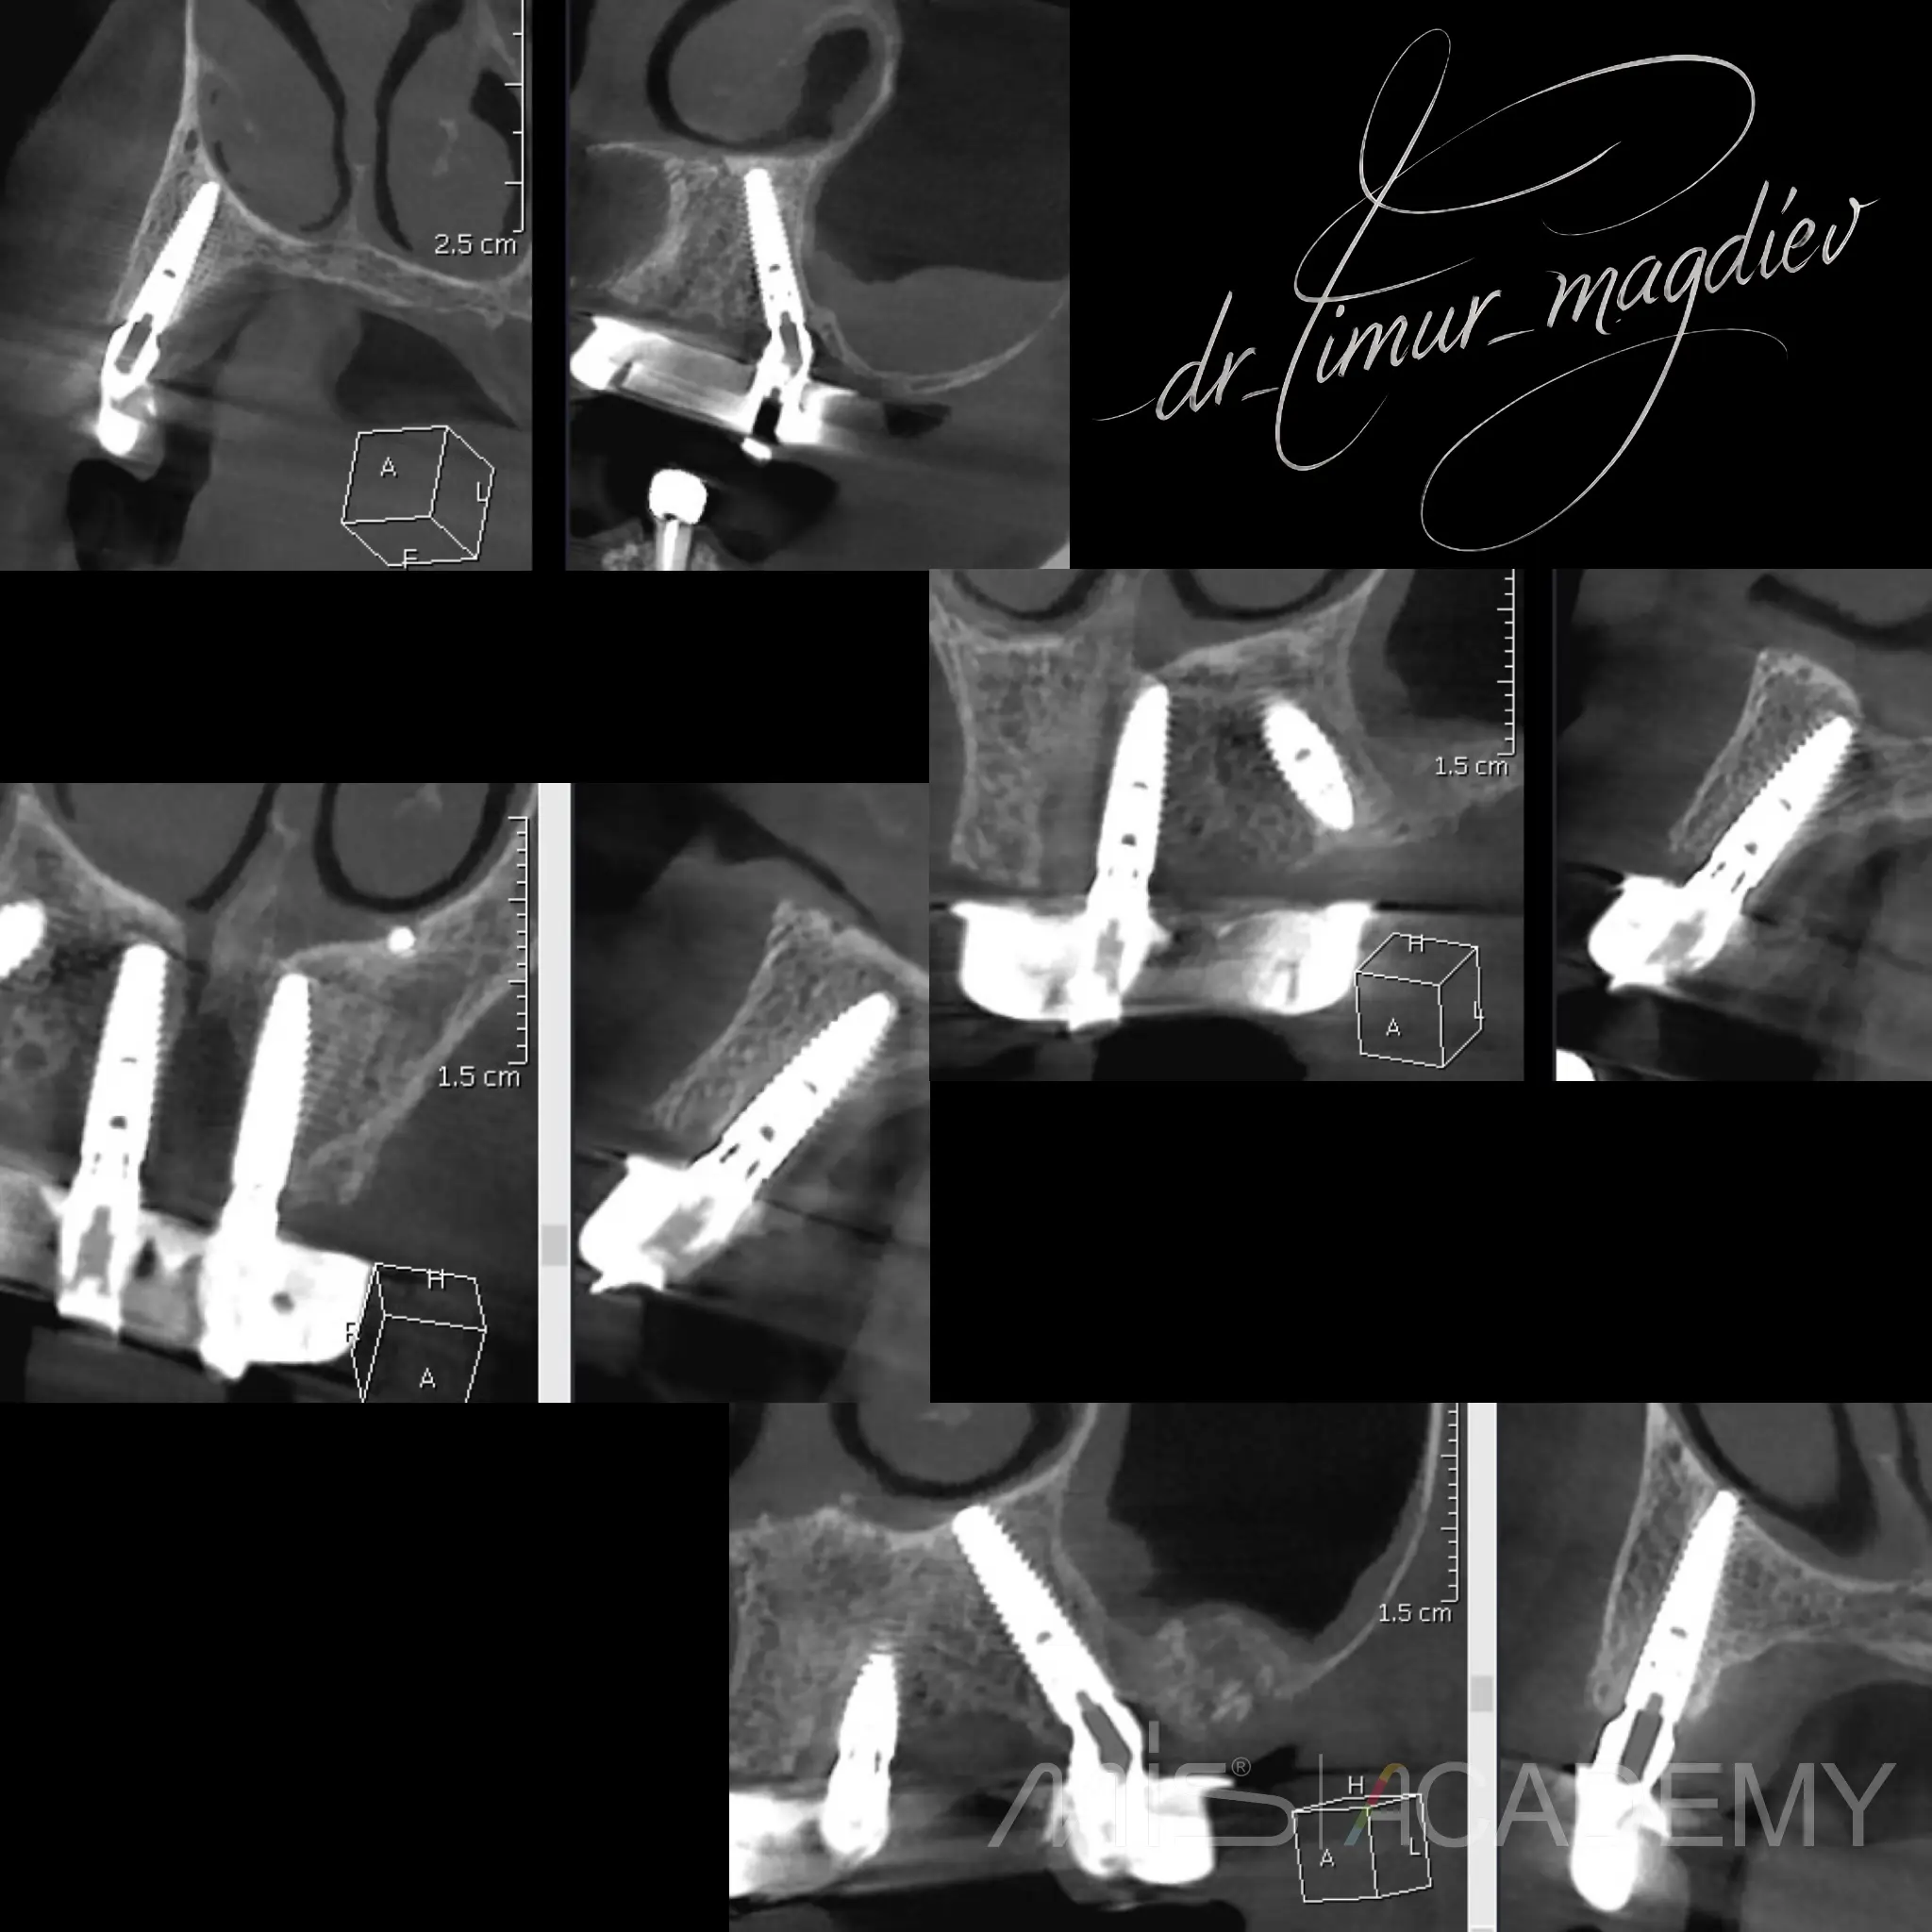

— Установка 4х имплантатов MIS с комбинированной установкой Connect и MU абатментов, в полном навигационном протоколе.

— Изготовление временного протеза в день операции.

— Протезирование титан акриловым протезом.